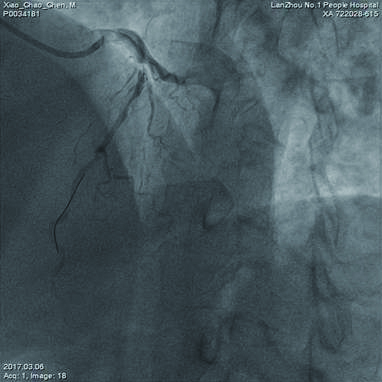

1 资料与方法患者,男性,62岁。曾因“反复胸闷、胸前区疼痛5月余”,就诊于当地医院。患者在住院期间病情加重,于2017年3月6日14:00以急性心肌梗死急诊转入甘肃省心血管病研究所。查体:血压88/45 mmHg,心率69次/min,双肺底部可听及中等量湿性啰音,心音低钝,心脏瓣膜听诊区未闻及病理性杂音,心电图异常,ST-T改变,提示前壁心肌梗死。抽血化验,立即送入导管室行紧急经皮冠状动脉介入治疗。冠脉造影提示:左前降支6段以后100%闭塞,前向TIMI血流0级,左回旋支100%阻塞,前向TIMI血流0级,右冠状动脉(RCA)2段60%狭窄,内膜不光整,前向TIMI血流2级(图 1)。

| 图 1 经皮冠状动脉介入治疗前左前降支与回旋支均完全堵塞,心肌梗死溶栓治疗血流0级 |